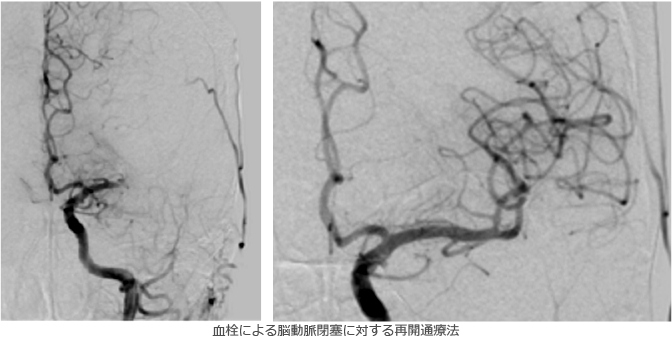

脳梗塞の治療に関しては、従来は脳梗塞の拡大・悪化を抑える点滴・内服とリハビリテーションによる機能回復が一般的でしたが、最近では発症後早期なら使用可能なt-PA療法(血栓を強力に溶かす点滴)や、カテーテルによる血栓回収・再開通療法が大きな効果を発揮するようになってきており、当院では24時間対応しております。また、内頚動脈狭窄症など脳梗塞の原因となりうる病変に対して行われる頸動脈ステント留置術(CAS)や、血管の慢性閉塞によって血流が足りなくなった部分に血流を補うバイパス手術などの治療も積極的に行っております。